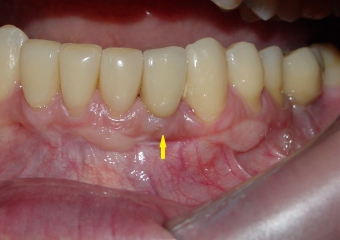

Imagem após extração do dente 32, devido a reabsorção radicular